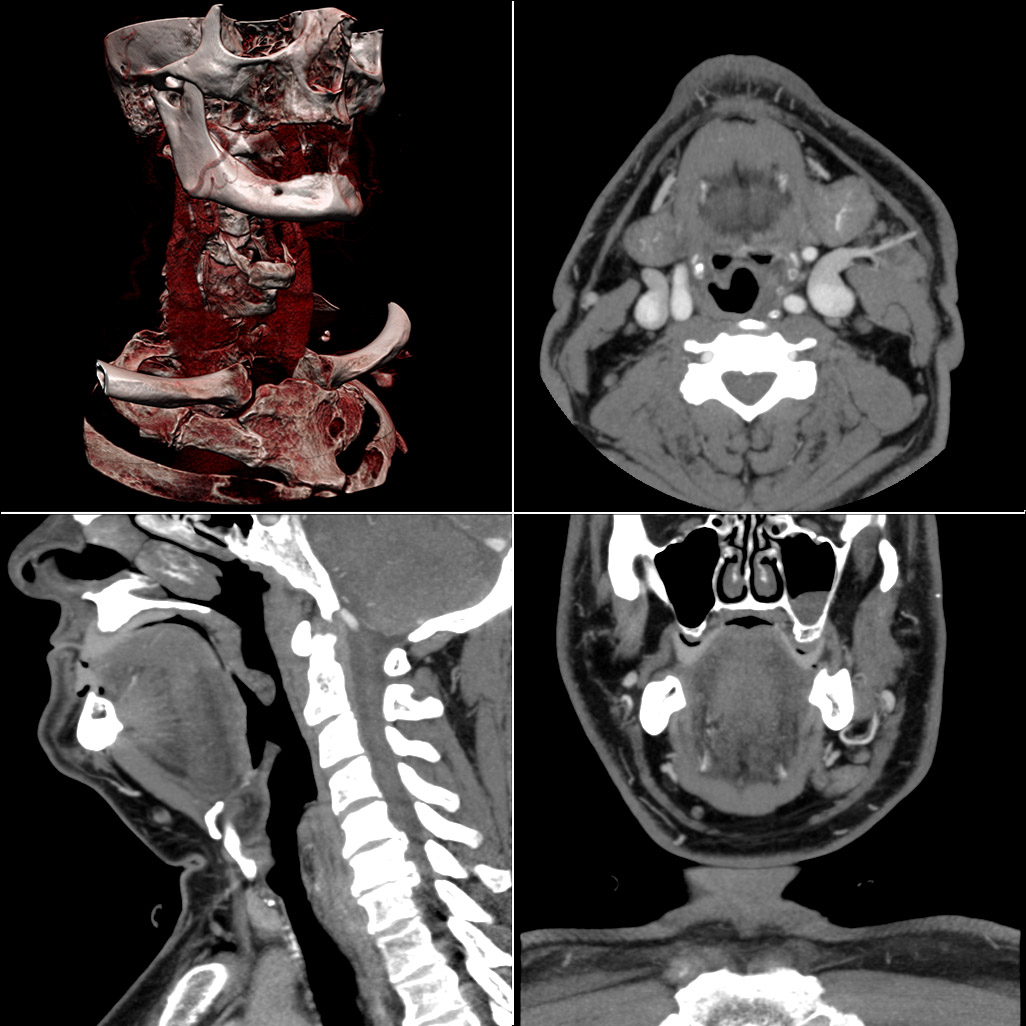

Компьютерный томограммы представляют собой карты распределения в плоскости томографирования коэффициентов ослабления рентгеновского излучения (см. рис. 6.20).

В настоящее время компьютерная томография подразделяется на пошаговую (традиционную) КТ, при которой одномоментно сканируется 1 томографический срез, и спиральную КТ, при которой данные снимаются со всего исследуемого объема, а затем из них реконструируются отдельные томографические срезы. Спиральная КТ, в свою очередь, подразделяется на односрезовую, при которой одновременно можно получить только один томографический слой и многослойную (мультсрезовую) КТ, при которой одновременно реконструируются от 2 до 64 томографических срезов.

Рис. 6.20. Многослойная («мультиспиральная») компьютерная томография с внутривенным контрастным усилением и трёхмерной реконструкцией изображения.